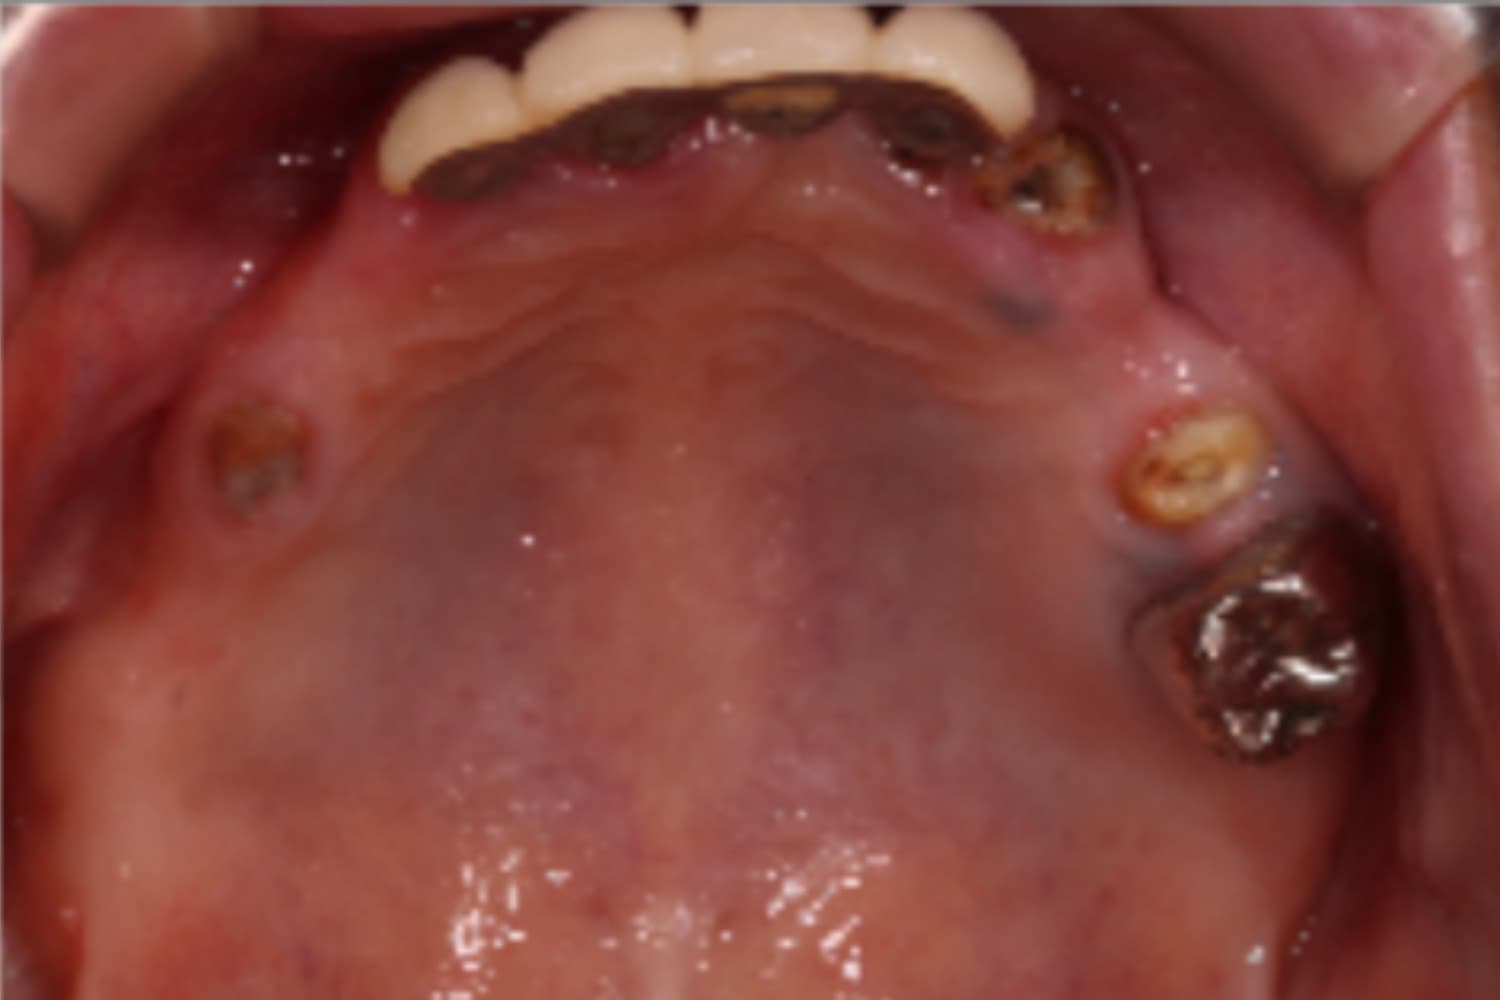

下顎すべてのインプラント治療

Before

After

下の前歯は抜歯と同時にインプラント4本を埋入し、その日に仮歯を装着してます(All-on-4)。

主訴

下の前歯がぐらぐらする

治療期間

6カ月

治療回数

12回

費用

3,080,000円

副作用・リスク

・インプラント埋入時の神経損傷リスクがあります。